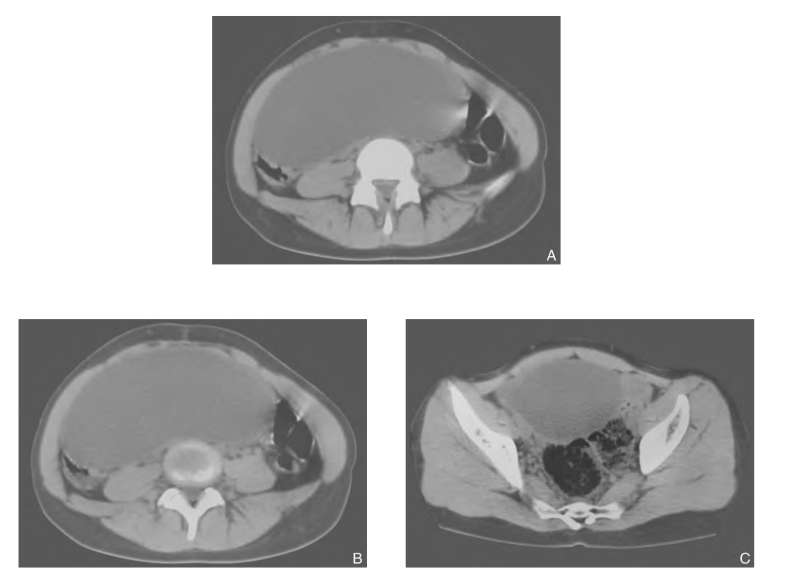

图4-22 右侧巨大卵巢囊肿

注:CT平扫示 盆腔右侧见一巨大囊性密度影,密度不均,其大小为7cm×15cm,境界清楚